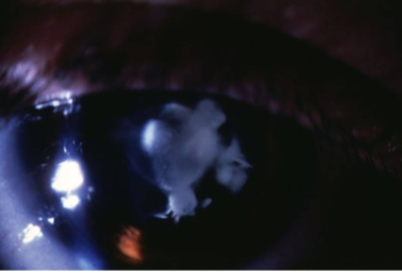

hypermature cataract

liquefication of lens fibers w/ leakage of H2O & protein

phacolytic uveitis & glaucoma

etiology:

hypermature cataract or ruptured capsule

inflammation secondary to the release of lens proteins

macrophages respond to the proteins & obstruct the TM

uveitis ocular signs

tx:

initial suppression of immune response w/ corticosteroids, then cataract extraction